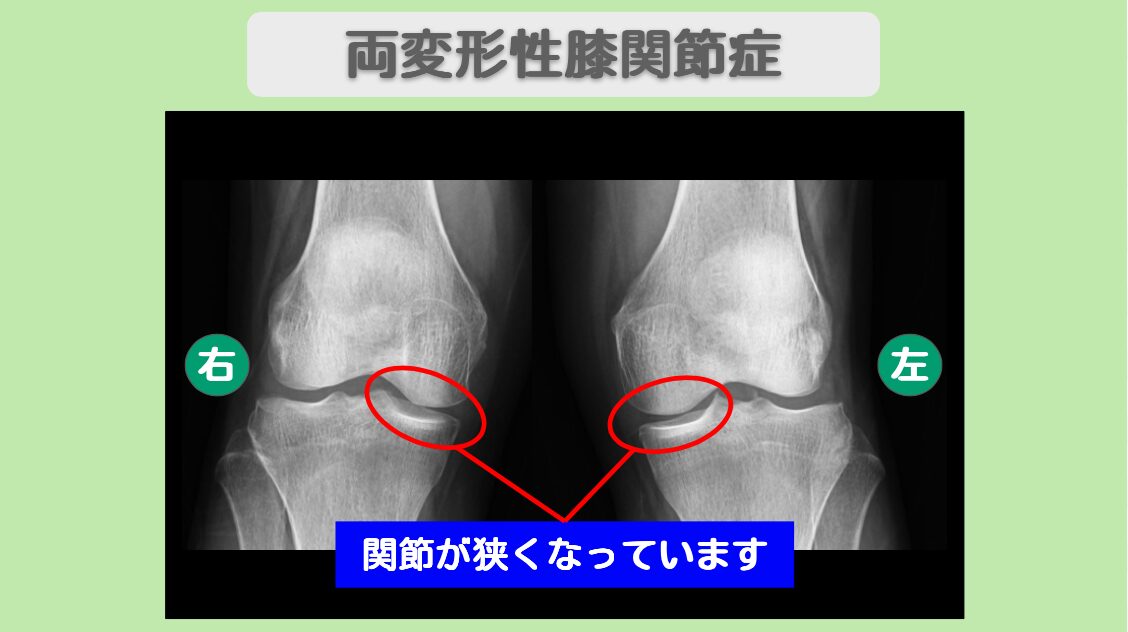

患者様は7年前にダンス中に右膝を負傷し、半月板損傷と診断されました。以降、2週間ごとにヒアルロン酸注射を継続するも、疼痛が持続していました。左膝にも10年以上前から痛みがあり、手術を勧められた経験があります。MRIでは右膝に広範囲の半月板損傷が確認され、レントゲンでは両膝に軽度の関節隙狭小化が認められました。ダンスインストラクターという膝に大きな負担のかかる職業のため、手術を回避しながら保存的治療を希望されて、当院にいらっしゃいました。

MRI・レントゲン所見

MRIにて半月板の損傷を認めます。